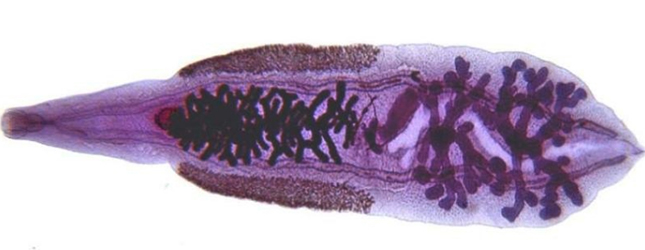

Паразитический организм под названием кошачья двустка или Opisthorchis felineus принадлежит к категории не шистосом. Его основным местоположением в организме является печень. Этот вид паразитов часто встречается на территории Европы и стран Ближнего Востока. Заразиться этим паразитом можно употребляя в пищу сырую или недостаточно приготовленную рыбу.

Opisthorchis felineus

Болезнь, вызываемая печеночными паразитами, известна как описторхоз. Попав в организм человека, черви перемещаются в желчные протоки, а затем в печень. Основная опасность этого заболевания заключается в том, что оно может длительное время протекать без симптомов, что может привести к развитию цирроза печени. Эффективность лечения напрямую зависит от скорости выявления инфекции.